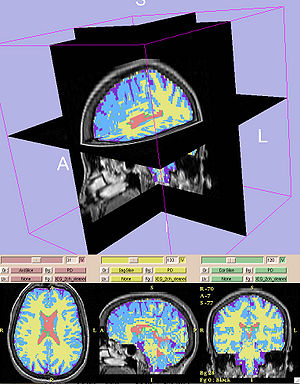

An Open Tool for Input Function Estimation and Quantification of Dynamic PET FDG Brain Scans

Publication: Int J Comput Assist Radiol Surg. 2015 Oct 29. PMID: 26514683 Authors: Bertrán M, Martínez N, Carbajal G, Fernández A, Gómez Á. Institution: Instituto de Ingeniería Eléctrica, Facultad de Ingeniería, Universidad de la República, Montevideo, Uruguay. Background/Purpose: Positron emission tomography (PET) analysis of clinical studies is mostly restricted to qualitative evaluation. Quantitative analysis of PET studies is highly desirable to be able to compute an objective measurement of the process of interest in order to evaluate treatment response and/or compare patient data. But implementation of quantitative analysis generally requires the determination of the input function: the arterial blood or plasma activity which indicates how much tracer is available for uptake in the brain. The purpose of our work was to share with the community an open software tool that can assist in the estimation of this input function, and the derivation of a quantitative map from the dynamic PET study. Methods: Arterial blood sampling during the PET study is the gold standard method to get the input function, but is uncomfortable and risky for the patient so it is rarely used in routine studies. To overcome the lack of a direct input function, different alternatives have been devised and are available in the literature. These alternatives derive the input function from the PET image itself (image-derived input function) or from data gathered from previous similar studies (population-based input function). In this article, we present ongoing work that includes the development of a software tool that integrates several methods with novel strategies for the segmentation of blood pools and parameter estimation. Results: The tool is available as an extension to the 3D Slicer software. Tests on phantoms were conducted in order to validate the implemented methods. We evaluated the segmentation algorithms over a range of acquisition conditions and vasculature size. Input function estimation algorithms were evaluated against ground truth of the phantoms, as well as on their impact over the final quantification map. End-to-end use of the tool yields quantification maps with relative error in the estimated influx versus ground truth on phantoms. CONCLUSIONS: The main contribution of this article is the development of an open-source, free to use tool that encapsulates several well-known methods for the estimation of the input function and the quantification of dynamic PET FDG studies. Some alternative strategies are also proposed and implemented in the tool for the segmentation of blood pools and parameter estimation. The tool was tested on phantoms with encouraging results that suggest that even bloodless estimators could provide a viable alternative to blood sampling for quantification using graphical analysis. The open tool is a promising opportunity for collaboration among investigators and further validation on real studies. |